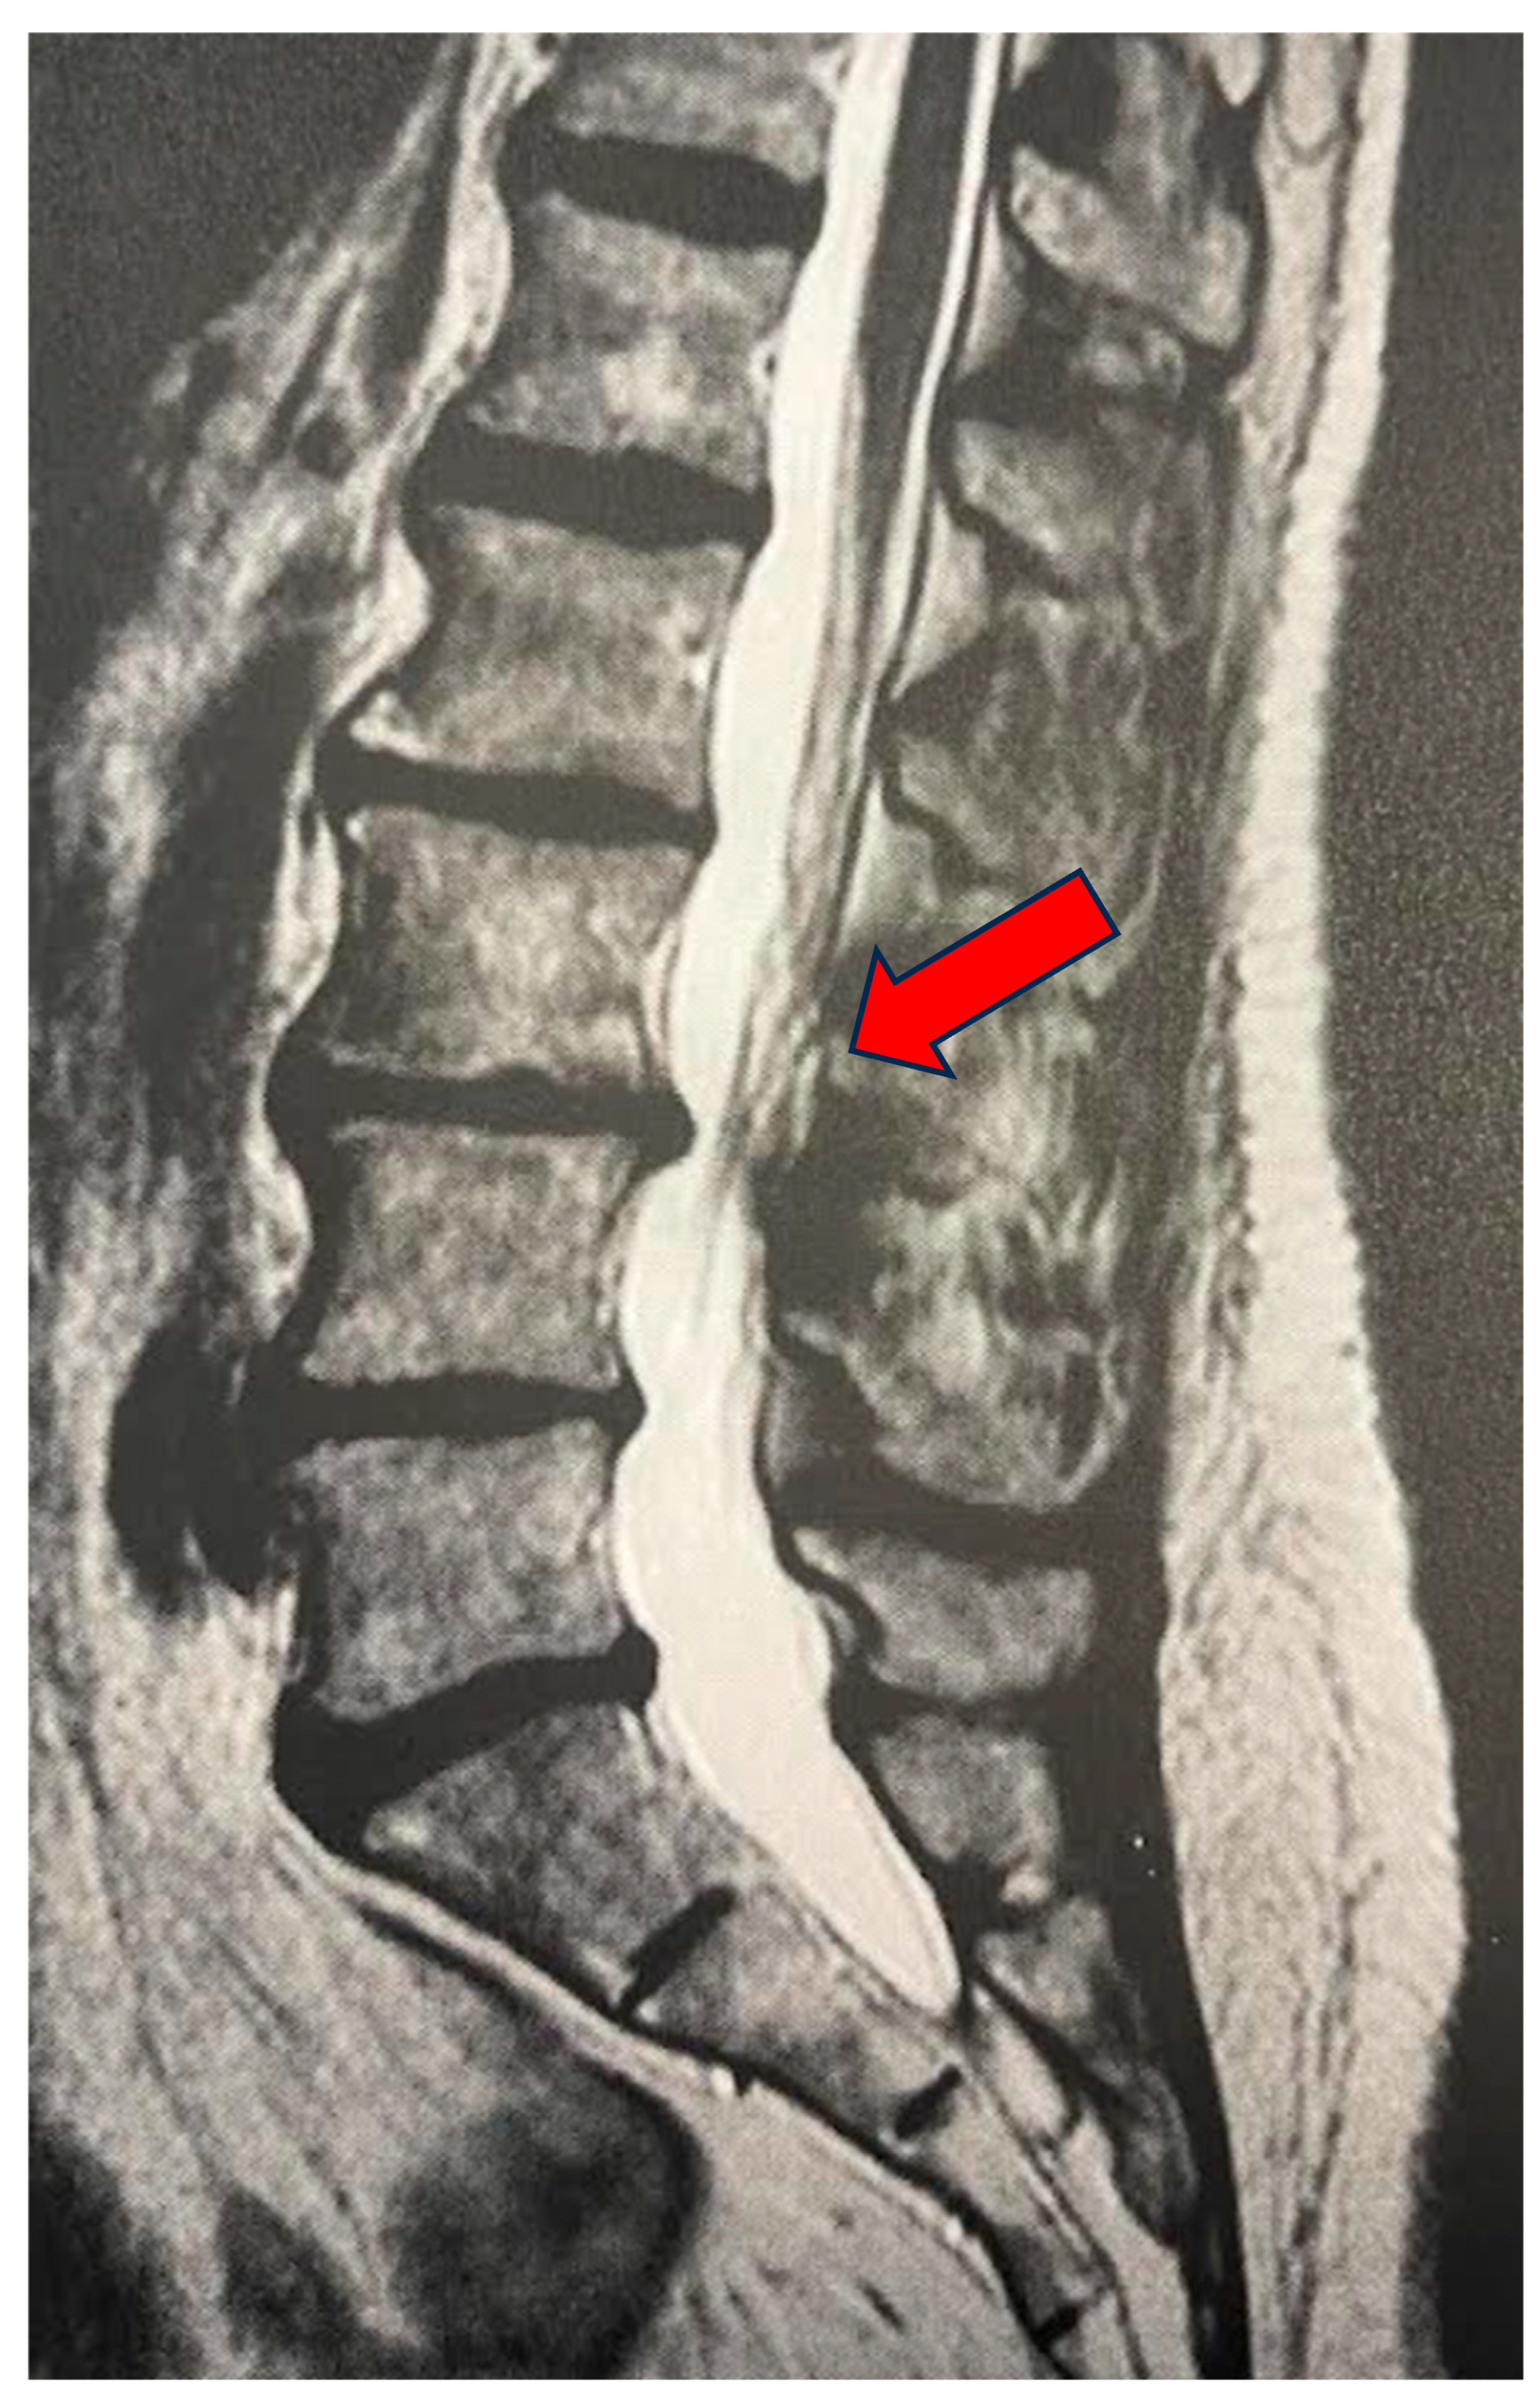

Figure 1.

LPR of 78-year-old female. Sagittal MRI: median subligamentous disc herniation at L3–L4 (arrow). Complete resolution of low back pain symptoms at both the one-month and one-year follow-up after treatment.